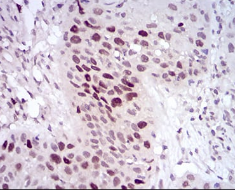

IHC    1/200 - 1/1000